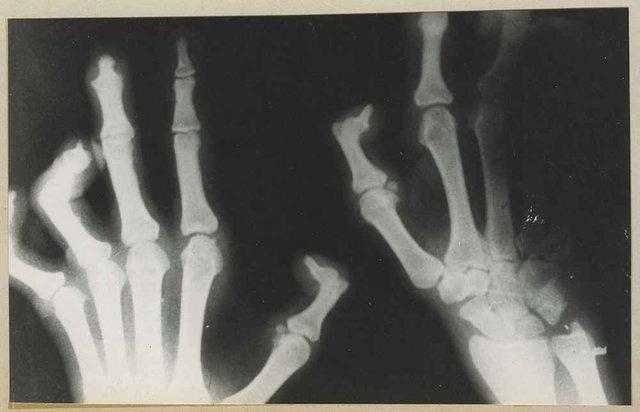

نشانههای اصلی بیماری به سه دسته عمده ضایعات پوستی، بیحسی و آسیب عصبی تقسیم میشوند و هر کدام خود را با علائمی نظیر لکههای پوستی معمولا در پوستهای تیره، از دست دادن حس (حرارت، درد و لمس سطحی و عمقی) و درگیری تنههای اعصاب محیطی به شکل تورم عصب، از دست دادن حس در پوست خود را نشان میدهند.

از ۷ مورد جدید کشف شده در سال ۱۴۰۱ همه موارد بالای ۱۵ سال سن داشتند و از نظر جنسیت ۲ نفر از آنها زن بودند. همه موارد جدید از نوع پرباسیل جذام بوده و ۳ مورد از ۷ مورد جدید گزارش شده دارای نقص عضو درجه دو بودند. همچنین هیچ یک از موارد جدید سابقه تماس نزدیک با بیمار مجذوم را ذکر نکردهاند.